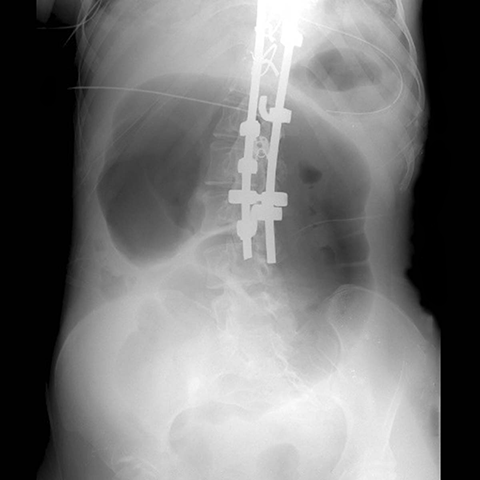

Cecal Volvolus, plain radiograph [2 of 3]